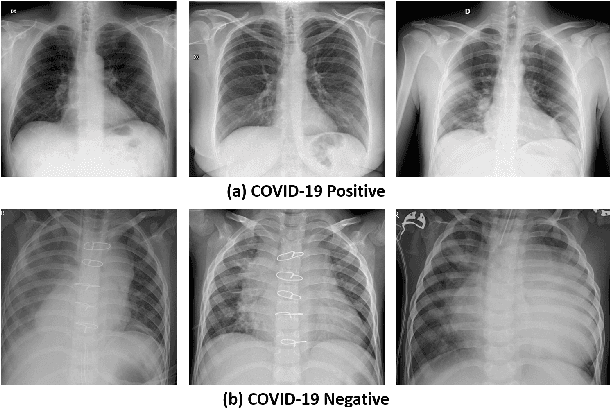

Abstract:Coronavirus Disease 2019 (COVID-19) pandemic rapidly spread globally, impacting the lives of billions of people. The effective screening of infected patients is a critical step to struggle with COVID-19, and treating the patients avoiding this quickly disease spread. The need for automated and scalable methods has increased due to the unavailability of accurate automated toolkits. Recent researches using chest X-ray images suggest they include relevant information about the COVID-19 virus. Hence, applying machine learning techniques combined with radiological imaging promises to identify this disease accurately. It is straightforward to collect these images once it is spreadly shared and analyzed in the world. This paper presents a method for automatic COVID-19 detection using chest Xray images through four convolutional neural networks, namely: AlexNet, VGG-11, SqueezeNet, and DenseNet-121. This method had been providing accurate diagnostics for positive or negative COVID-19 classification. We validate our experiments using a ten-fold cross-validation procedure over the training and test sets. Our findings include the shallow fine-tuning and data augmentation strategies that can assist in dealing with the low number of positive COVID-19 images publicly available. The accuracy for all CNNs is higher than 97.00%, and the SqueezeNet model achieved the best result with 99.20%.